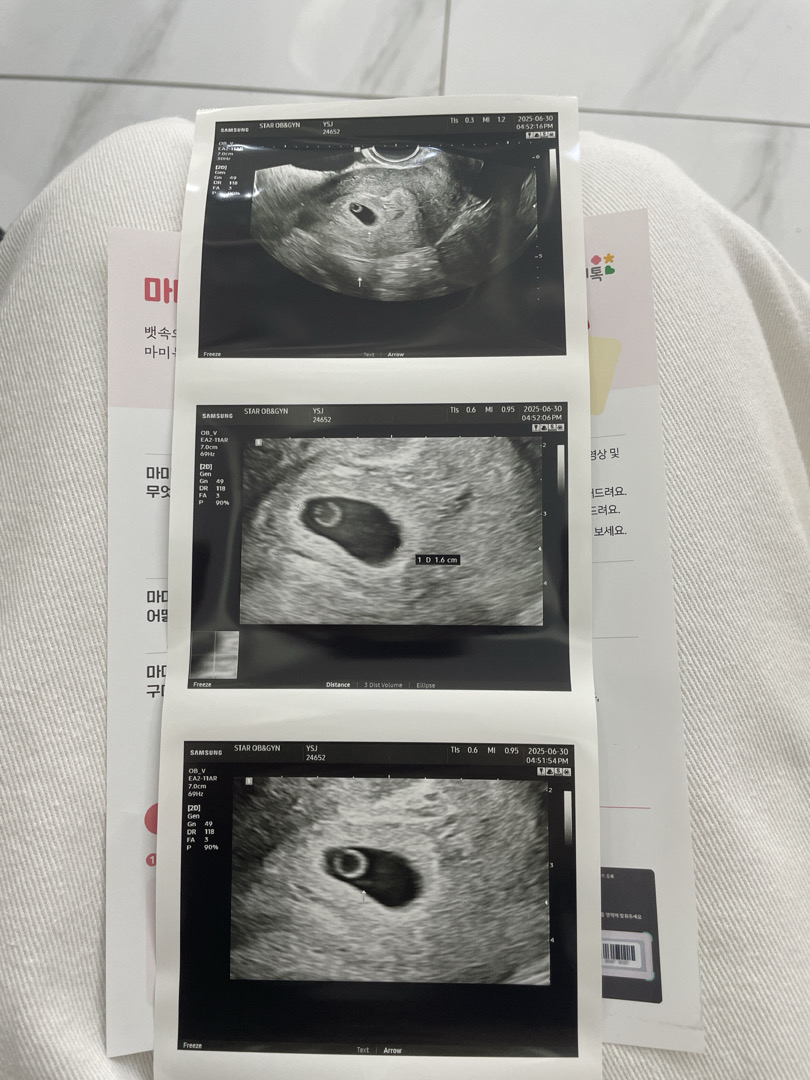

6주 0일 아기집과 난황

4주 때 병원가서 아기집 못보고 피검사로만 수치 확인했었는데 오늘 6주차 병원갔다왔어요! 아기집이랑 난황이 너무 뚜렷하게 잘 보였어요🥹 촘파 보시고는 5주차 예상된다고 하시더라구용?! 이주뒤에 오면 심장소리랑 아기 보고 예상 주수를 말씀해주신다고 하시더라구옹 넘 기대되어요🤭